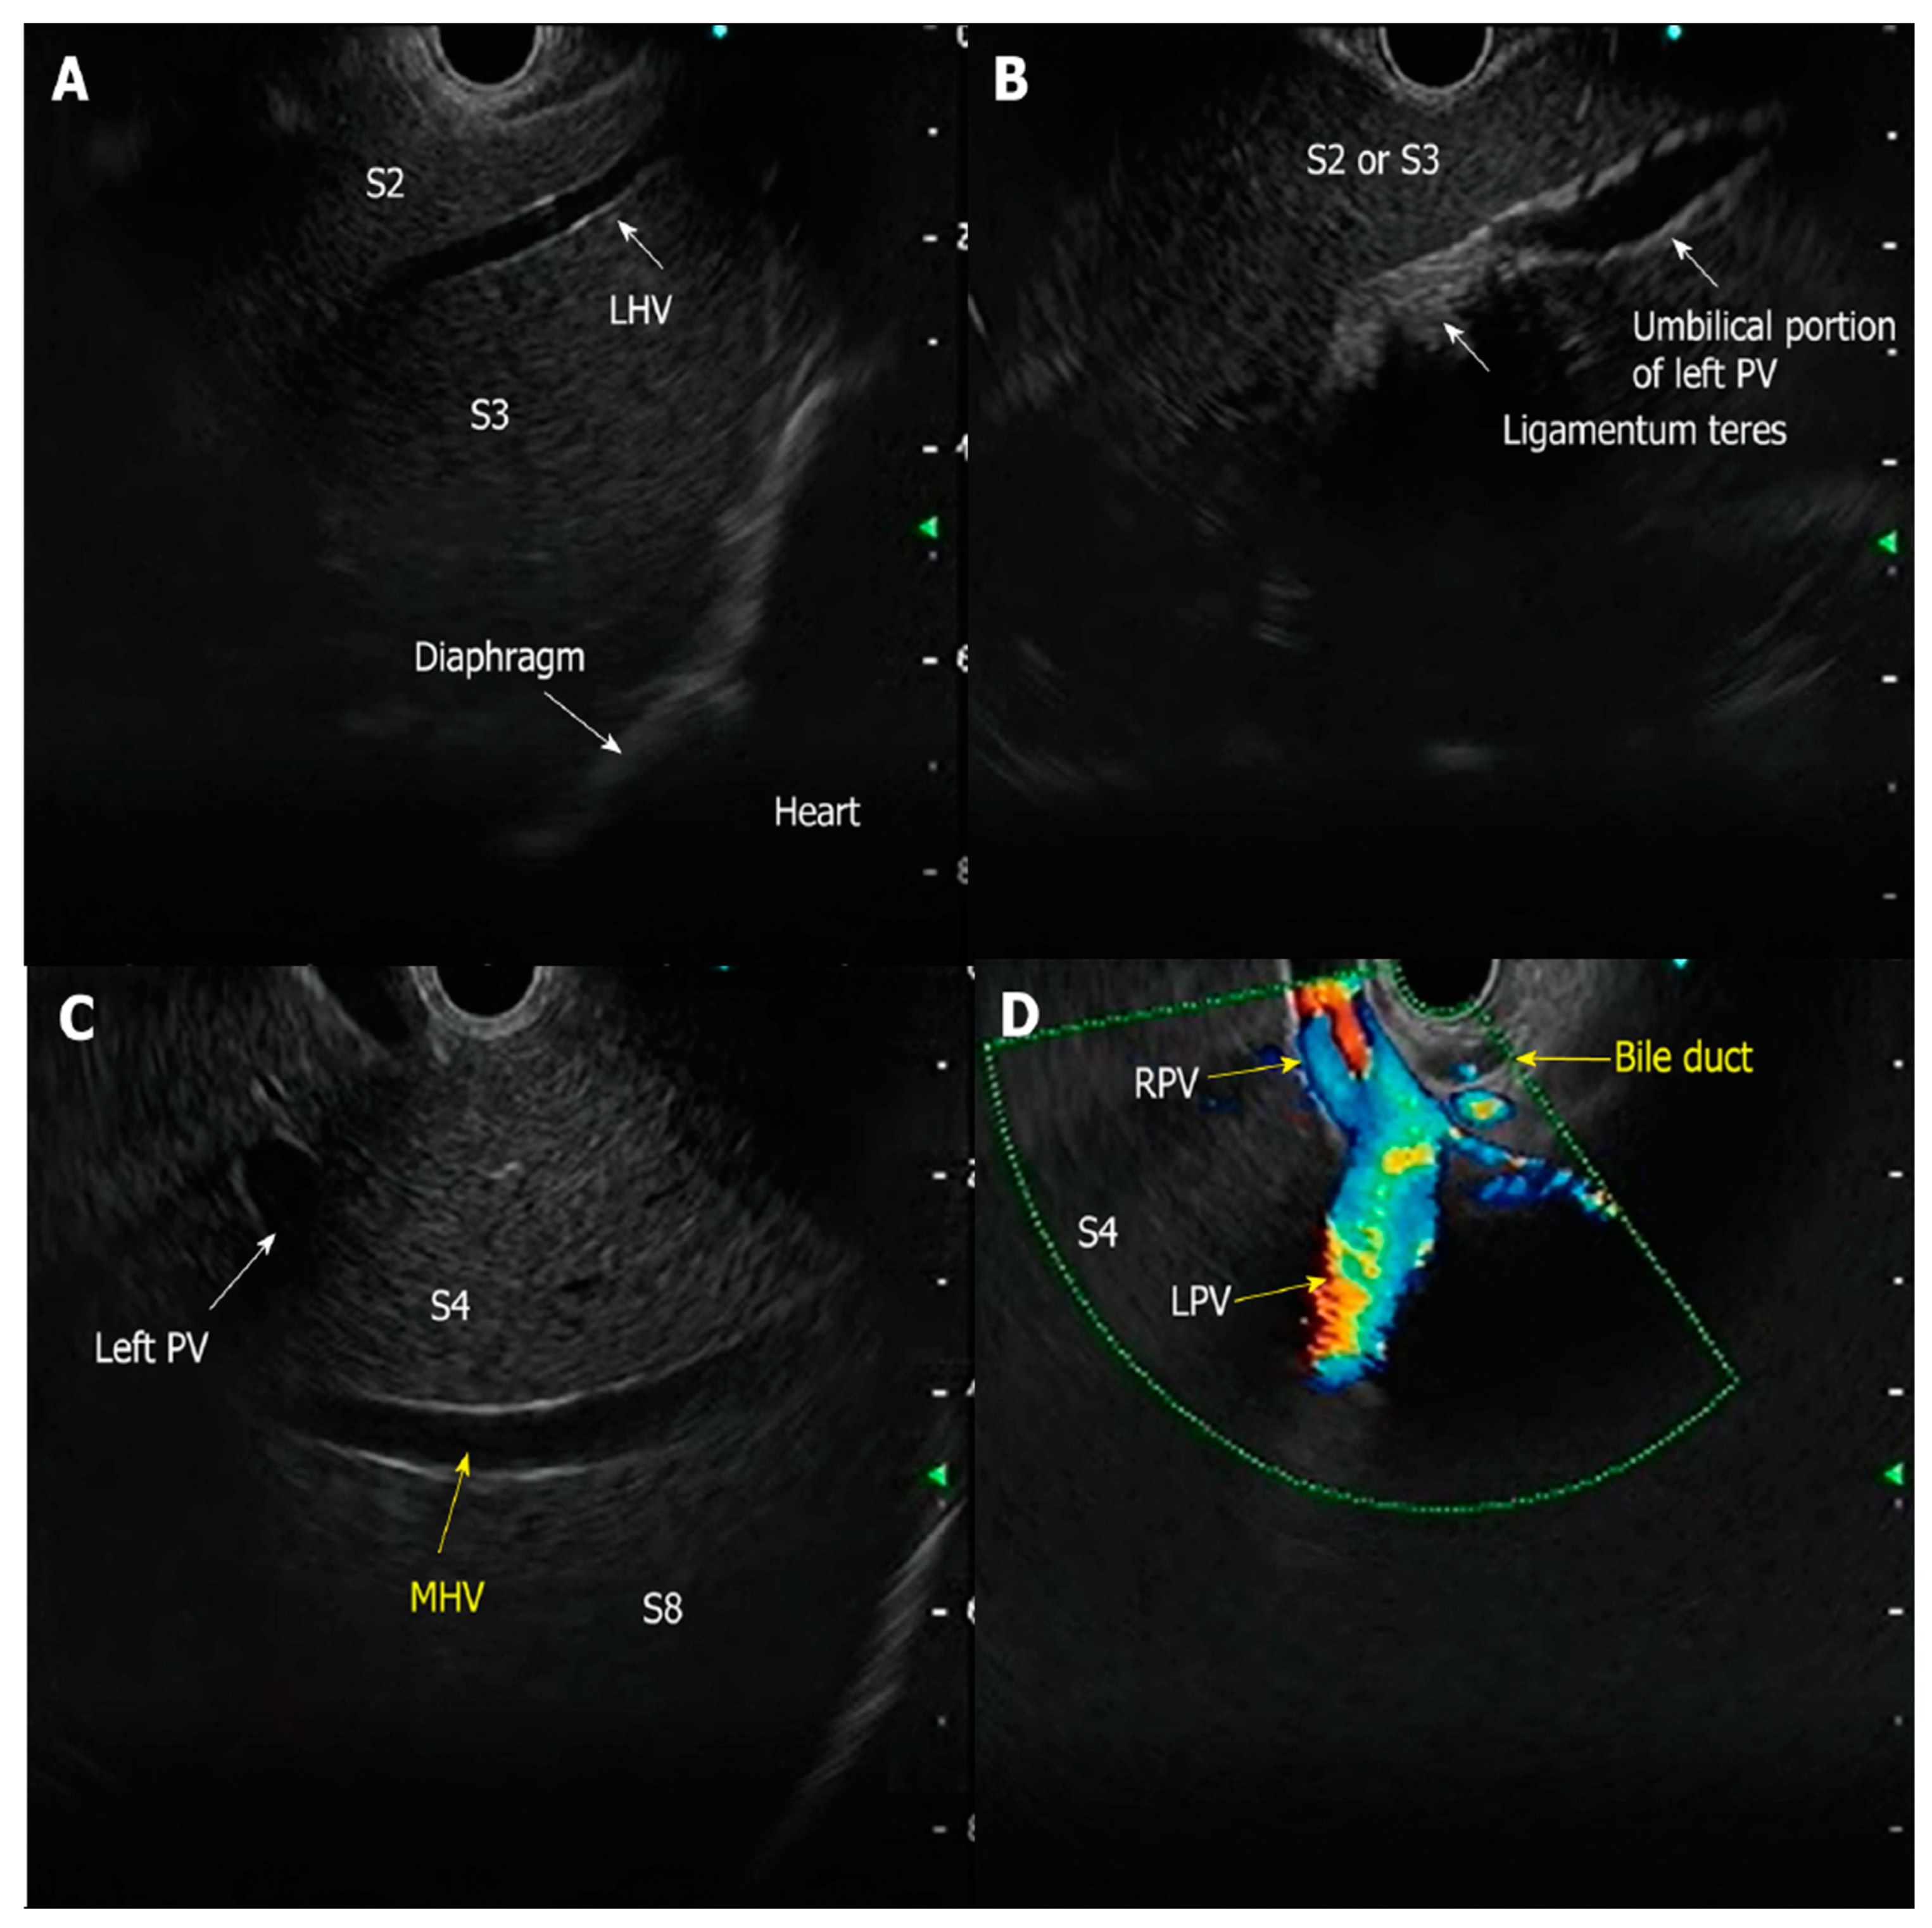

- Simons-Linares, C.R.; Wander, P.; Vargo, J.; Chahal, P. Endoscopic ultrasonography: An inside view. Cleve Clin. J. Med. 2020, 87, 175–183. [Google Scholar] [CrossRef] [PubMed]